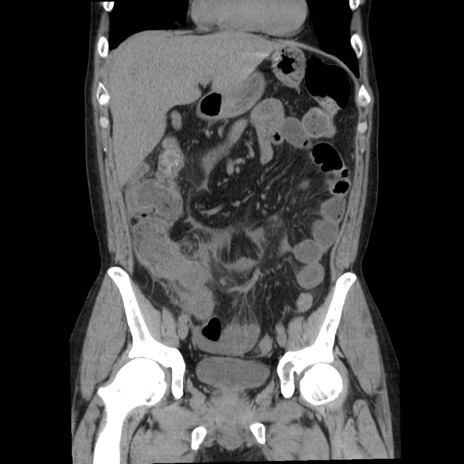

症例29(冠状断像)

【症例】40歳代男性

【現病歴】2日前から胃痛あり。徐々に周期的な激痛に変化した。本日になっても激痛があるため受診。

【身体所見】意識清明、BT 38-39℃台あり、腹部:膨満、やや硬、右下腹部に圧痛あり。

【データ】WBC 8500、CRP 23.26